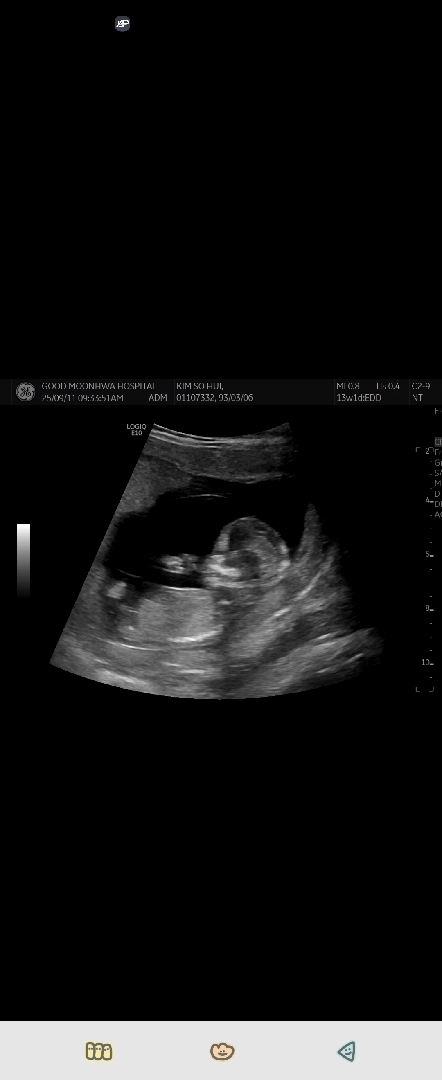

13주차 성별 봐주세요❤️

이 사진으로 보일까싶은데...ㅎㅎ 그래도 선배님들께 의견을 묻고싶습니다!!

램지법으로 딸이요